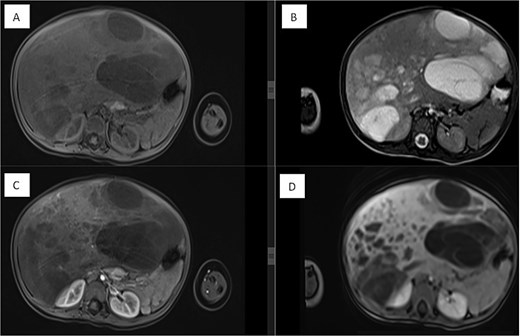

Final histopathological examination of the resected 17 cm mass confirmed the diagnosis of HMH (Figs 4 and 5). The patient recovered well postoperatively.

(A) Histological section showing interspersed islands of hepatocytes with retention of normal cell plate architecture (hematoxylin & eosin, 6.23×). (B) Myxoid area with benign duct structures and interspersed normal hepatocytes (hematoxylin & eosin, 6.98×). (C & D) Dilated and branching bile ducts show no cytological atypia (hematoxylin & eosin: C- 18.55×, D- 7.05×).

(A & B) Vimentin immunostain demonstrating positive cytoplasmic staining in neoplastic cells (6.26×). (C) CK7 immunostain highlights the benign bile duct epithelium (3.64×). (D) GLUT1 immunostain shows negative staining in neoplastic cells and positive staining in red blood cells (internal control) (11.44×).